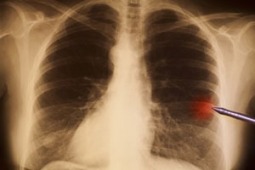

Afatinib i erlotynib w leczeniu zaawansowanego raka płuca - wyniki badania LUX-Lung 8

Źródło: Afatinib versus erlotinib as second-line treatment of patients with advanced squamous cell carcinoma of the lung (LUX-Lung 8): an open-label randomised controlled phase 3 trial Soria, Jean-Charles et al. The Lancet Oncology , Volume 16 , Issue 8 , 897 – 9

W magazynie Lancet opublikowano wyniki próby klinicznej III fazy.